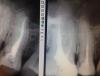

Денис481 Опубликовано 22 января, 2013 Поделиться Опубликовано 22 января, 2013 вот пришел пациент,где то налечили его,болит зуб,сделал снимок (справа фото),перелечил,после смотрел снимок,(слева),и по-моему даже 80%, что там 2 канала,мой силлер зашел туда,что скажете? Ссылка на комментарий

x3m Опубликовано 22 января, 2013 Поделиться Опубликовано 22 января, 2013 (изменено) чувство не подводит если к чувствам добавить еще и контуры периодонталок и апексов - мы увидим, что там два отдельных апекса.Соответственно, каналов тоже два. Изменено 22 января, 2013 пользователем x3m 1 Ссылка на комментарий

Afffinity Опубликовано 22 января, 2013 Поделиться Опубликовано 22 января, 2013 Похоже что действительно 2. И апекс открывается сбоку как и на пройденном канале. Ссылка на комментарий

Денис481 Опубликовано 22 января, 2013 Автор Поделиться Опубликовано 22 января, 2013 По первому снимку не скажешь,не бросается в глаза,поэтому и не сразу увидел Ссылка на комментарий

diesel87 Опубликовано 23 января, 2013 Поделиться Опубликовано 23 января, 2013 Если не ошибаюсь, пятерка верхняя, там по умолчанию на 2 канала настраиваешься сразу. Да и по 1-ому снимку 2 апекса просматриваются. Ссылка на комментарий

x3m Опубликовано 23 января, 2013 Поделиться Опубликовано 23 января, 2013 вот, все отлично видно.совет из практики: знание анатомии, понимание индивидуальных особенностей и снимки в 2 проекциях с отклонением в 30 градусов помогут в поиске прекрасного (всех каналов то бишь). на первом снимке видно хуже, но двоение периодонтальных щелей на нем должно наталкивать на поиск чего-то дополнительного. 1 Ссылка на комментарий